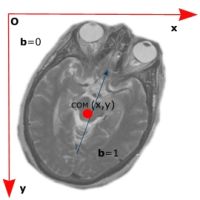

To calculate the center of mass (COM), the method uses the right hand convention in 3D coordinate systems (X, Y, Z). Thus, in the image space, the left hand corner of the image is set to (0,0,0). The x axis goes left to right, y axis goes top to bottom and z axis goes into the screen.

Figure 2. Calculating the center of mass (COM)